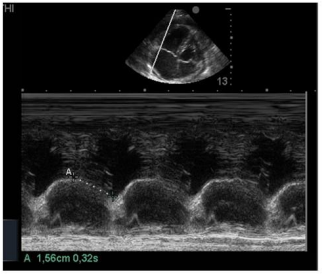

Na insonação cardíaca beira-leito, a mensuração da excursão do anel da tricúspide (TAPSE) resultou em 1,56 cm como demonstrado na imagem apresentada. Isso significa ventrículo direito